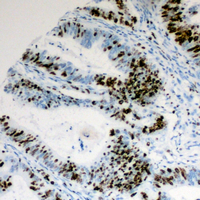

IHC (Immunohiostchemistry)

(Immunohistochemical analysis of Cyclin E1 (pT395) staining in human colon cancer formalin fixed paraffin embedded tissue section. The section was pre-treated using heat mediated antigen retrieval with sodium citrate buffer (pH 6.0). The section was then incubated with the antibody at room temperature and detected using an HRP conjugated compact polymer system. DAB was used as the chromogen. The section was then counterstained with haematoxylin and mounted with DPX.)